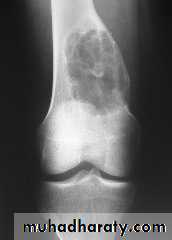

Rx : curettage + bone graftPicture 4. Frontal radiograph of the right thigh demonstrates coarse calcifications in the distal femur.